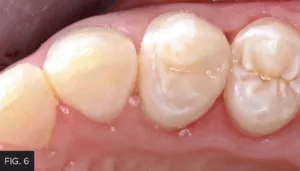

The post-operative result shows a smooth and ideal contour with a tight interproximal contact. (FIG. 6) These characteristics are critical in obtaining a result that yields easy cleansability and less potential for postoperative sensitivity. Utilizing the DualForce Matrix System allows for a predictable and reliable outcome to help achieve clinical success for your patients.